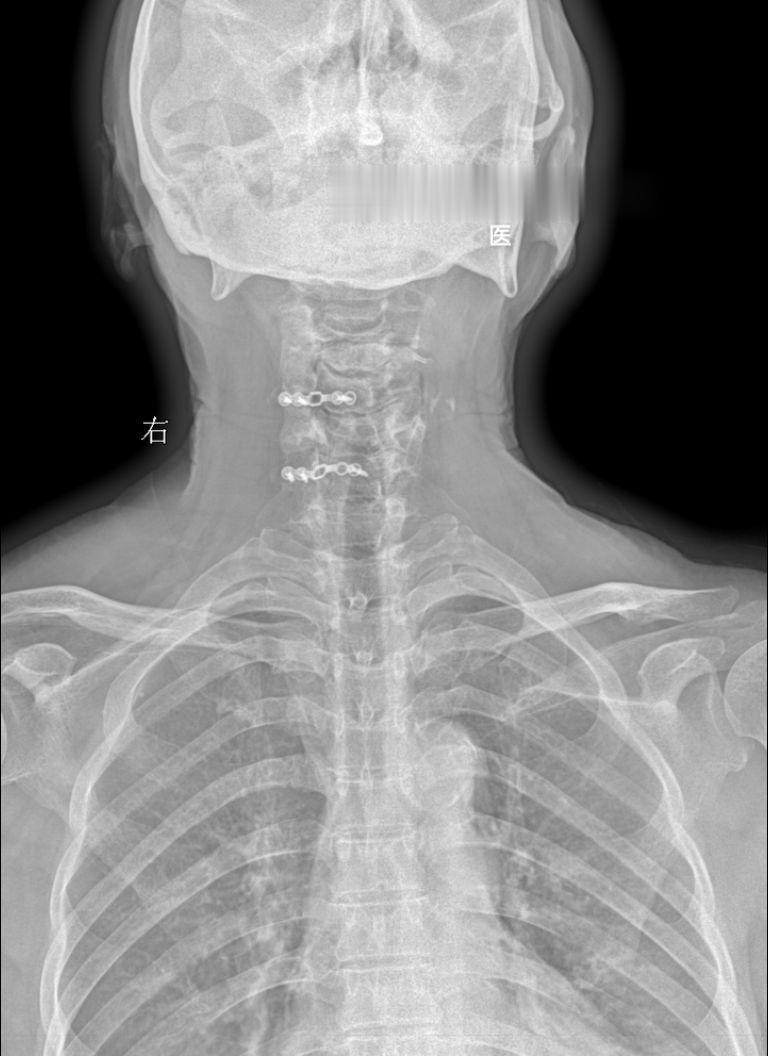

体征:车祸术后两年,颈椎疼痛就诊